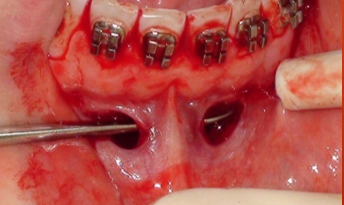

- Incision

Horizontale au bistouri sur environ 10mm le long du repli du fond vestibule, jusqu'au contact osseux.

- Rugination

Sur environ 5mm afin de mettre l’os à nu au-delà des apex pour pouvoir placer la vis.

- Vissage de la ou des vis et plaquage du fil contre la corticale osseuse

Le geste peut être réalisé quasiment en aveugle car il n’y a aucun risque anatomique pour les structures sous-jacentes.

Le bras de la connectique est libéré de l’encoche du tournevis par un simple mouvement de doigt dès que la vis commence être vissée dans la corticale.

Le vissage est réalisé jusqu'à ce que la vis paraisse entraîner la connectique dans sa rotation. Elle est alors légèrement desserrée pour permettre de la repositionner avant son serrage final.

Dans le cas d’une boucle un 8, le serrage final de la première vis n'est réalisé que lorsque la seconde a elle-même été posée.